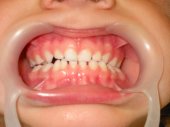

Las fracturas de los incisivos superiores en

la infancia son accidentes lastimosos que suceden con una alta frecuencia.

El tratamiento atento y cuidadoso ahorrará muchos sufrimientos

y frustraciones al paciente.